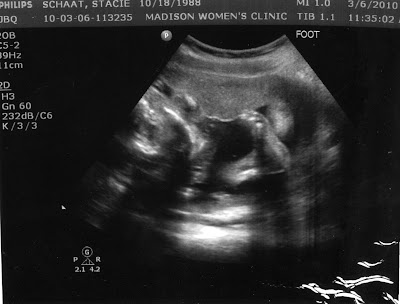

They started with the ultrasound and our sweet little baby girl seems to be doing perfectly, as usual. I was excited to hear that she is weighing in at 3 lbs. 9 oz. Happy Stacie. Unfortunately, when my bp reading was 168/114 I was immediately checked into the hospital for 24 hour monitoring of myself and the baby. The doctor told me that if I had another high reading like that in the next 4 hours I would be classified with severe preeclampsia and sent to the

On a much happier note, with all of the ultrasounds that we have been getting we've heard countless compliments about how fantastic our little munchkin is doing.

"Wow. Can you see her breathing?" (This one was my favorite, the doctor literally had a look of amazement as we watched her breathe. I'm glad to know her lungs are impressive, because they develop last)